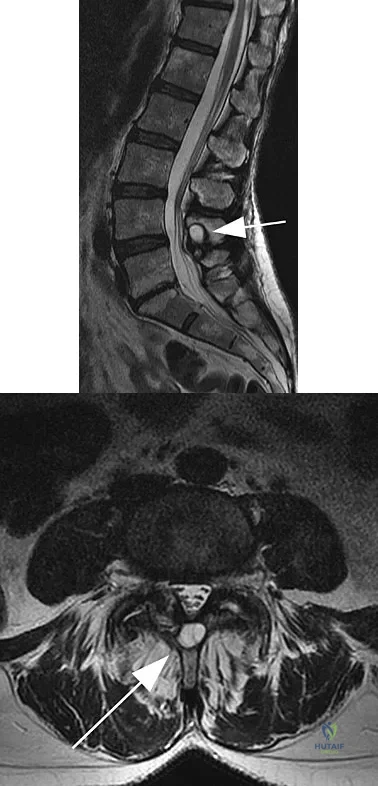

A 25-year-old tennis player has shoulder pain and weakness to external rotation. MRI scans are shown in Figures 16a and 16b. What is the most likely cause of his weakness?